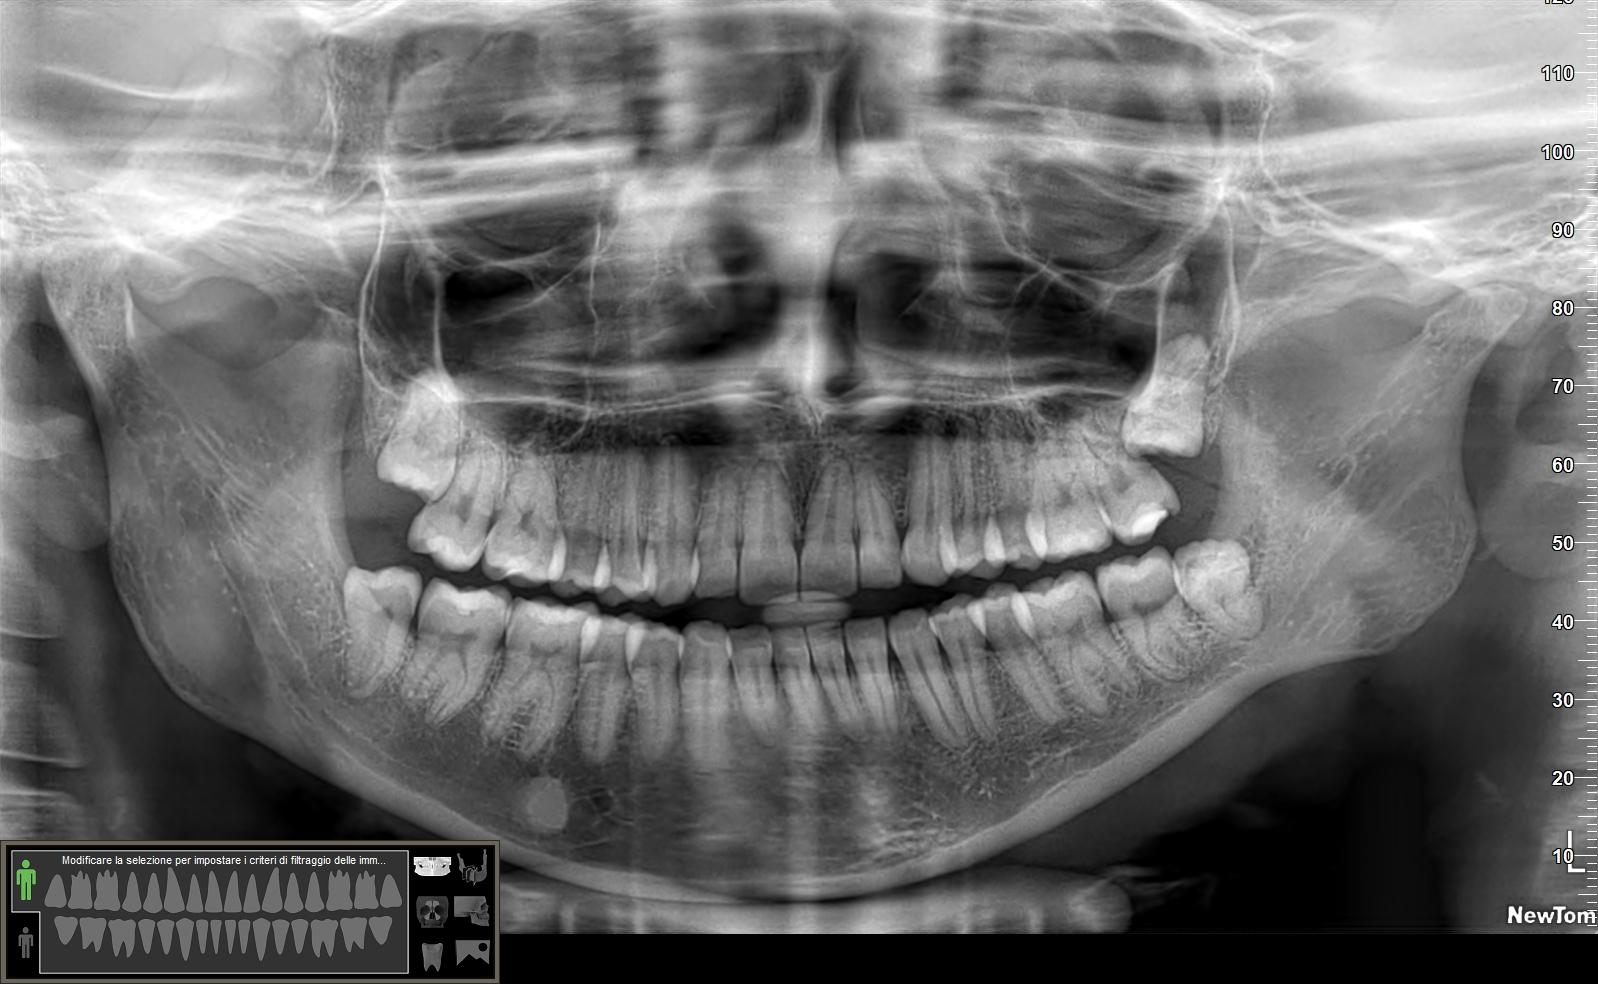

Buonasera Dottore, vorrei chiederle un parere su tutti e 4 i denti del giudizio.

Mi è stato detto che sono tutti e 4 “tragici”, però i 2 superiori e quello inferiore sinistro possono aspettare per l’estrazione, mentre quello inferiore destro (quello dal lato della scritta “NewTom”) andrebbe estratto subito e dalla TAC si vede che è vicino o addirittura tocca il nervo mandibolare (non ho ben capito) e per quest’ultimo motivo non ho il coraggio di estrarlo, perché rischio una lesione del nervo mandibolare e perché alla fine non mi reca fastidio e mi è stato detto che potrebbe rimanere fermo così come è, cioè senza crescere ulteriormente e quindi senza andare a tagliarmi la lingua, inoltre ho letto che è possibile anche che estraendo ad esempio l’inferiore, quello superiore potrebbe scendere più del dovuto e quindi poi dovrei togliere anche quello superiore.

Non sono tutti e quattro tragici. Alla sinistra della radiografia sono tranquillissimi sia sopra che sotto mentre alla destra, dove c’è la scritta “New Tom” da problemi solo il dente del giudizio inferiore che però non sembra avere una radice così “cattiva”. Bisognerebbe comunque fare prima una TAC per capire quali sono i reali rapporti del nervo con la radice che spesso appare sovrapposto ma in realtà è semplicemente dietro o davanti la radice stessa e con un po’ di attenzione si può fare un’estrazione senza particolari complicanze. In casi particolarmente sfortunati e meglio magari fare una coronectomia, intervento che comunque preserva il nervo da eventuali danni. Io ne ho fatte parecchie è solo il rado ho avuto problemi. Comunque se non sembrano messi così male ovvero non sembra che possano danneggiare i denti vicini (cosa per la quale si renderebbe necessaria l’estrazione anche senza sintomi). Quindi aspettare direi che è la cosa più saggia. Ovvio che se poi incominciano infezione ricorrenti la scelta finisce e bisogna agire.